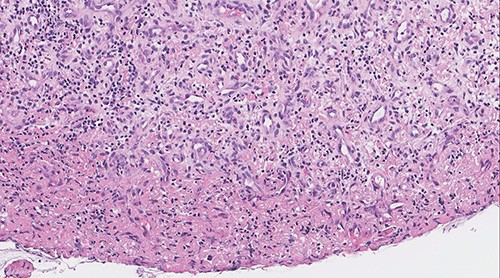

The post-operative course was uneventful, and the patient was discharged the same day with analgesics and anti-reflux medications. The patient was given appointment for follow in otolaryngology clinic one week after discharge for pathology review and reassessment. Pathology report revealed lobular capillary hemangioma with no evidence of malignancy. Histologic sections showed polypoidal squamous mucosa with associated superficial ulceration and fibrinoid necrosis (Figs 7 and 8). Submucosally, there was proliferation of small blood vessels arranged as lobules with surrounding granulation tissue and chronic inflammatory cells (Fig. 9). The endothelial cells were bland, spindled and lack dysplastic features. No atypical mitotic figures were identified. The squamous epithelium adjacent to the ulceration showed hyperplastic changes. After 2 months patient was re-evaluated again and reported improvement of his symptoms. Examination showed normal larynx with no signs of recurrence.

Vascular proliferation arranged as lobules with adjacent chronic inflammation (original magnification: X200, H&E stain).